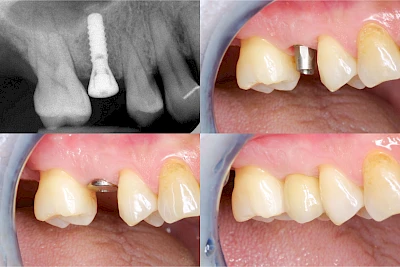

Implantate sind künstliche Zahnwurzeln. Nach einer gewissen Einheilzeit im Knochen (meist 3-6 Monate) erfolgt über einen separaten Aufbau (Abutment) die Befestigung einer Krone bzw. Brücke oder Zahnprothese.

Implantate: Kronen & Brücken

Fehlen einzelne Zähne und die Nachbarzähne sind unbeschadet oder gut zahnärztlich versorgt, werden immer häufiger Implantate gewählt, um die Lücken zu schließen. Auch bei größeren oder verteilten Lücken, wenn keine herausnehmbare Prothese gewünscht ist, werden Implantate für Kronen- bzw. Brückenversorgungen gesetzt. In Einzelfällen entscheiden sich sogar zahnlose Patienten für eine festsitzende Versorgung auf Implantaten.

Varianten zur Verankerung von festsitzendem Zahnersatz auf Implantaten